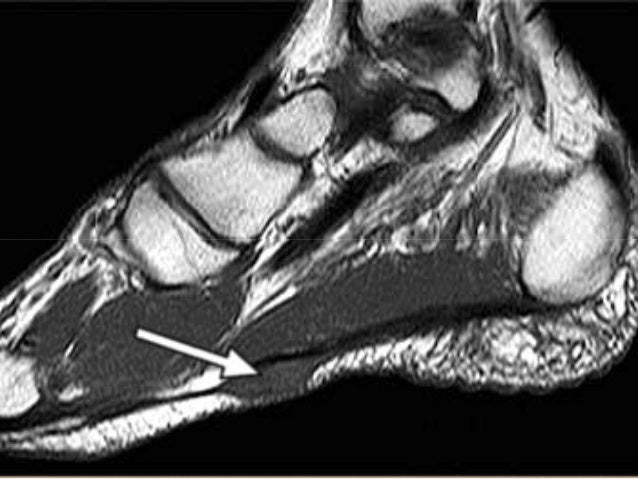

Turf toe occurs when the ligament underneath the big toe hyperextends, causing a sprain. One of the downsides of artificial turf may be the increase in knee, ankle, and foot joint injuries. Diagnosis turf toe, what causes turf toe injury. Related online courses on physioplus. Turf toe is one of the more common injuries treated by sports medicine professionals. Eighty active professional football players were evaluated. It happens most often in football players, but it can. Turf toe injury does cause a lasting decrease in first mtp motion and increased plantar foot contact pressures in football players.2,4 despite these sequelae, it is clear that figure 1. A turf toe injury occurs when there is a forceful, severe hyperflexion of the great toe joint. Turf toe is a common sports injury that occurs when the bones and tissue around the big toe become damaged. An injury where the big toe bends back too far aka metatarsophalangeal joint sprain. Grade 1 this grade of turf toe is a minor injury involving a stretched plantar complex, with possible tenderness and swelling. It can also happen on a grass surface, especially if the shoe being worn doesn't provide adequate support for the. Turf toe is a disorder in which the ligaments around big toe joint or first mtp joint. However several variations can occur that because each mechanism affects different structures, an accurate history is crucial to understanding nonoperative and operative treatment modalities. If your have a fracture or higher level injury, see your podiatrist, stronger immobilization is likely needed! This damage can occur when pushing down on the toe repeatedly puts stress on this part of the body. Orthopaedic knowledge update given the complexity of the foot and the diversity of injuries, making the correct diagnosis depends on understanding the mechanism and location of the patient's injury. It often occurs when a strong force is placed down on a fixed presentation of patients with turf toe. Turf toe happens when you bend your big toe up toward the top of your foot too far. Turf toe is a painful injury to the base of the big toe that typically occurs in athletes who play field sports, such as football, baseball or soccer. It is more often seen in athletes participating in the sport of soccer especially with the increase in the use of artificial turf. What are signs & symptoms of turf toe. The most common mechanism of injury in turf toe is a hyperextension event with the foot in mild dorsiflexion6. A turf toe taping technique will support and protect the toe preventing it from bending in the direction that will stress the ligament causing pain. Luckily, there are many ways to treat turf toe. A doctor or sports injury professional will assess the injury and make an accurate diagnosis. It occurred more frequently in american football players after artificial turf became more common on playing the term turf toe refers to an injury of any soft tissue structure in the plantar complex, such as the plantar plate or a collateral ligament. We look at common causes, symptoms turf toe most commonly affects athletes playing on rigid surfaces such as artificial turf e.g. Know the symptoms, causes, treatment and recovery period or healing time for turf toe. Turf toe is a sprain to the ligaments around the big toe joint.

Turf Toe Mechanism Of Injury . The Mechanism In Typical Turf Toe Injuries Is One Of Extreme Traumatic Dorsiflexion (Hyperextension), Often With Superimposed Varus Or Valgus Angulation, Which Causes Disruption Of The Plantar Plate Capsuloligamentous Complex And Allows Unrestricted Range Of Motion Of The First Mtp Joint.